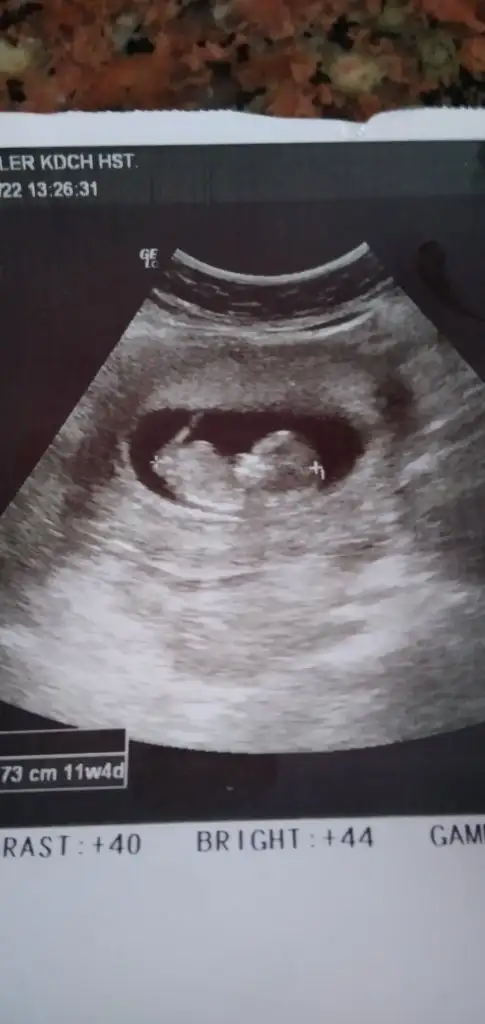

Canim banada bakarmisinErkek tabiki en iyi 11 12 13 haftalar olmalı

Şimdilik kız yönünde ama en iyi 11 12 13 haftalar olmalı üsten baktı ise kız alttan baktı ise erkekCanim banada bakarmisinEki Görüntüle 2976264